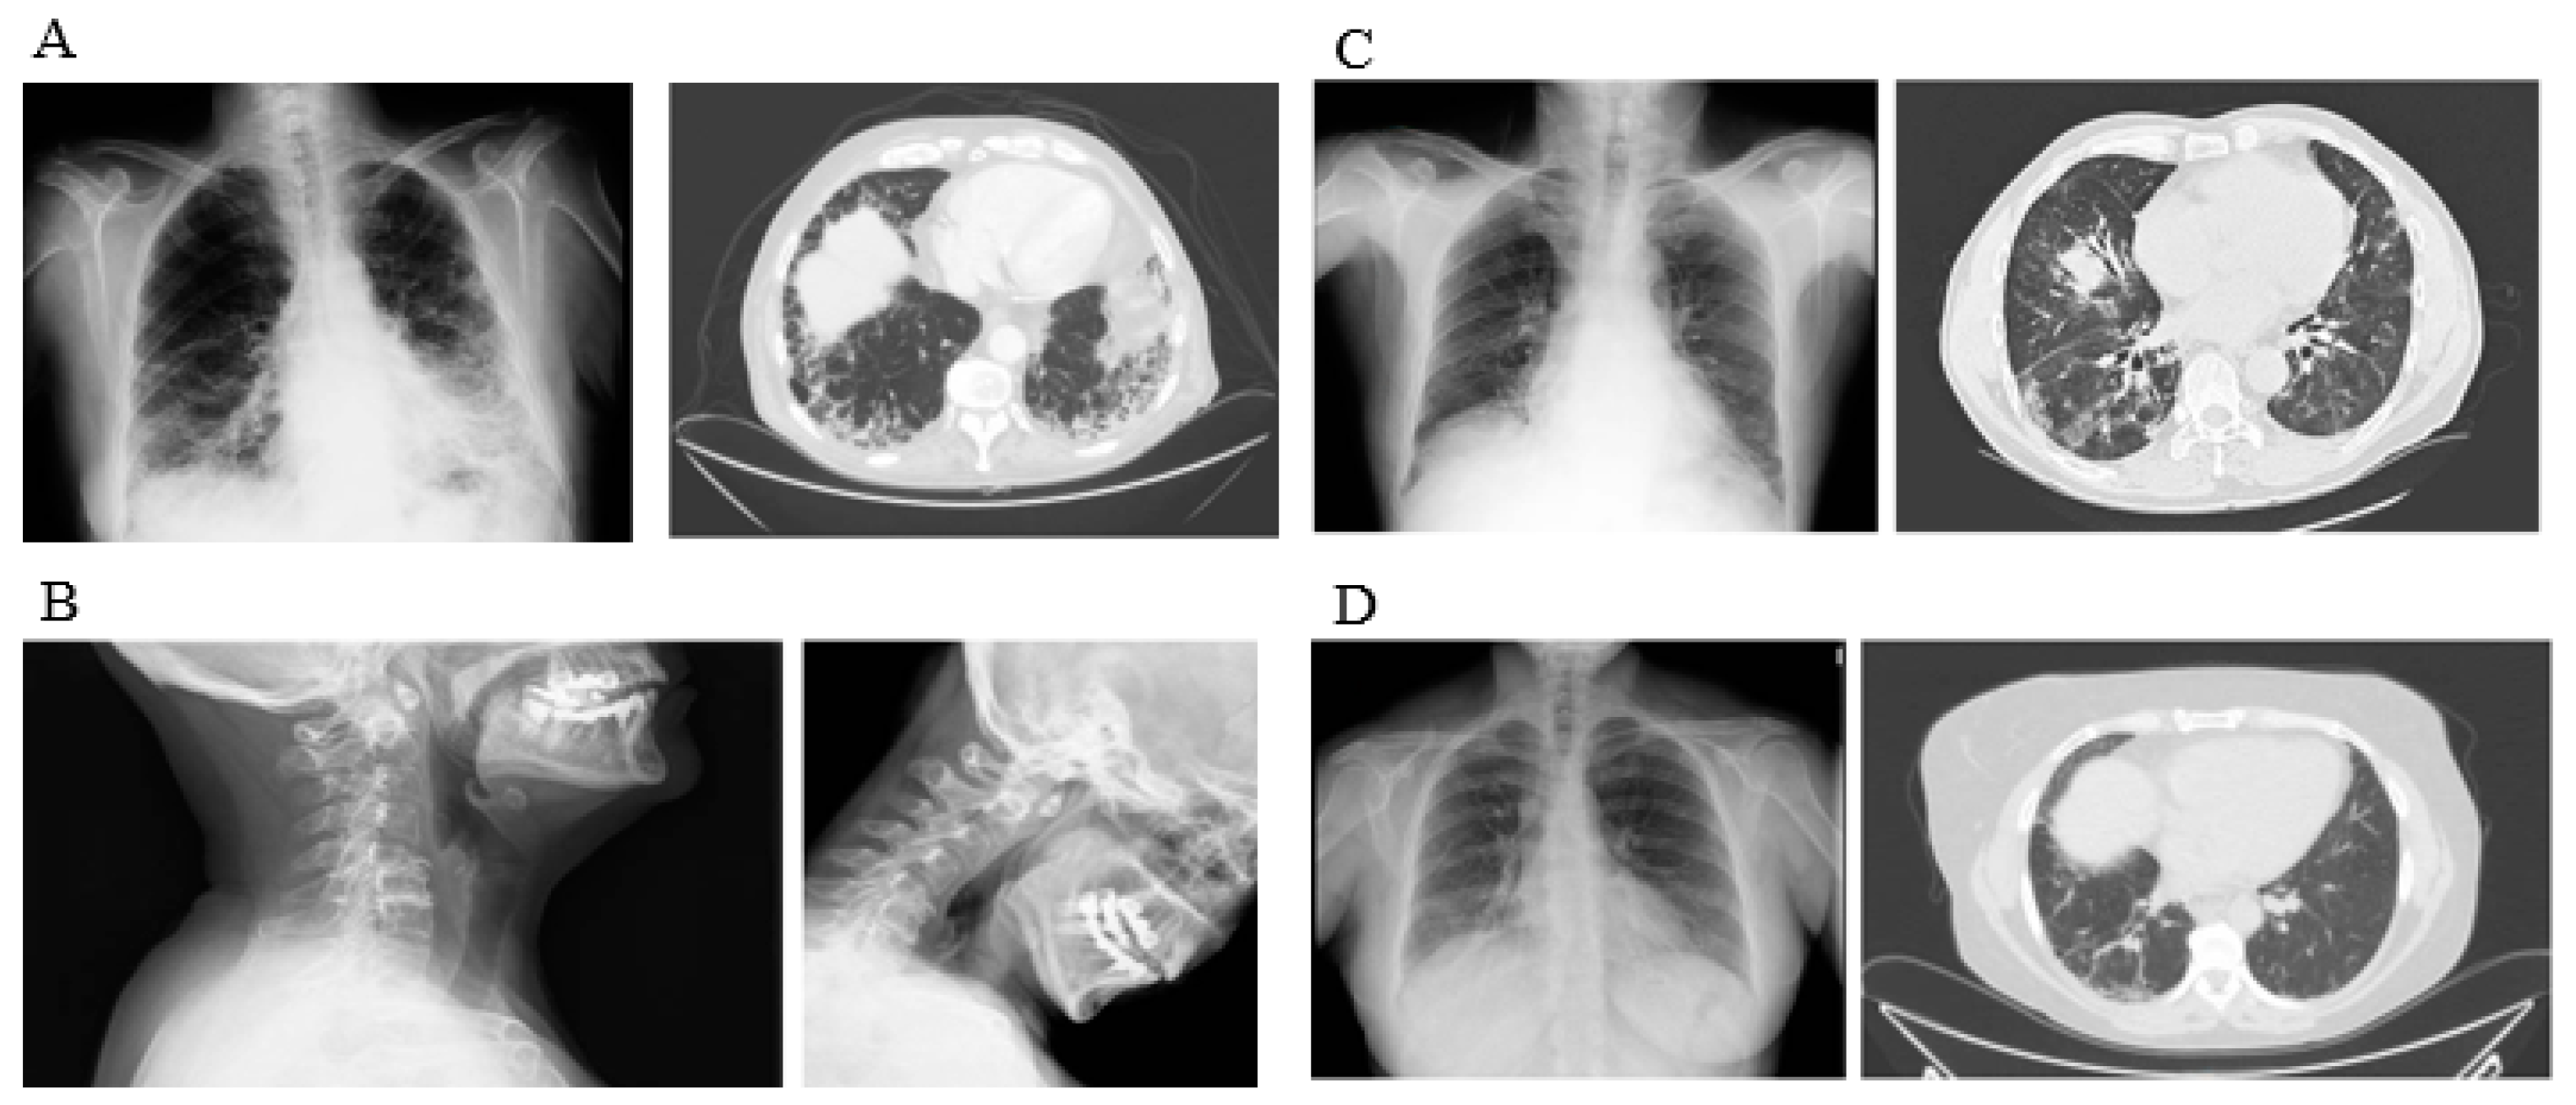

| HRCT pattern | ||||||

| Radiologic pattern | <0.001 | |||||

| UIP, n (%) | Baseline | 86 (42.1) | 74 (60.1) | 2 (8.7) | 10 (17.2) | |

| Final | 91 (44.6) | 77 (62.6) | 2 (8.7) | 15 (25.8) | ||

| NSIP, n (%) | Baseline | 101 (49.5) | 35 (28.5) | 20 (86.9) | 46 (79.3) | |

| Final | 99 (48.5) | 33 (26.8) | 20 (86.9) | 42 (72.4) | ||

| Fibrotic NSIP, n (%) | Baseline | 10 (4.9) | 7 (5.6) | 1 (4.3) | 2 (3.4) | |

| Final | 7 (3.4) | 6 (4.8) | 1 (4.3) | 1 (3.4) | ||

| Other types, n (%) | Baseline | 7 (3.4) | 7 (5.6) | 0 (0.0) | 0 (0.0) | |

| Final | 7 (3.4) | 7 (5.6) | 0 (0.0) | 0 (0.0) | ||

| Progression by HRCT | 0.002 | |||||

| Progression, n (%) | Final | 72 (35.3) | 48 (39.0) | 4 (17.4) | 20 (34.5) | |

| Stabilization, n (%) | Final | 93 (45.6) | 60 (48.8) | 7 (30.4) | 26 (44.8) | |

| Improvement, n (%) | Final | 39 (19.1) | 15 (12.2) | 12 (52.2) | 12 (20.7) | |